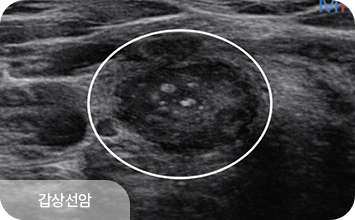

갑상선에 생긴 혹을 갑상선결절이라 하며, 이 중 악성이 바로 갑상선암입니다.

갑상선암은갑상선암은 완치율이 높아 ‘착한 암’으로 불리기도 하지만

방치할 경우 다른 부위로 전이될 수 있으므로 조기 발견과 적절한 치료가 중요합니다.

특히 여성에게 더 흔하게 발생하므로 정기적인 검진이 필요합니다.

갑상선 질환은 결절의 크기보다,

구조적 특성과 변화 양상을 함께 살펴야 합니다.